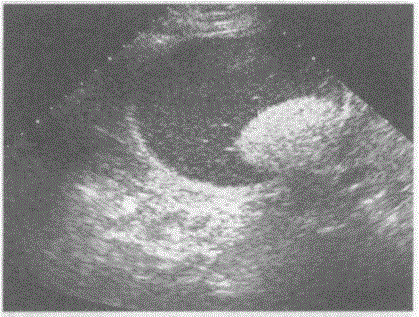

问题 临床资料:女,29岁,体检发现右附件区肿物。 超声综合描述:子宫形态大小正常,肌层回声均匀,子宫内膜居中。右附件区可见无回声区,边界清晰,形态规则,内透声不清亮,可见点状中强回声及团状强回声。 超声提示:

选项 A.右卵巢畸胎瘤(面团征) B.右卵巢巧克力囊肿 C.右卵巢囊腺瘤 D.右卵巢囊腺癌

答案 A